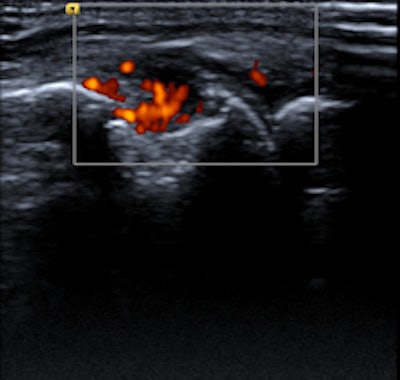

Elderly patient with established and treated rheumatoid arthritis. The patient complained of increased pain and stiffness. Ultrasound shows active synovitis and erosions in multiple metacarpo-phalangeal joints (a = grayscale image, b = power Doppler image). Ultrasound is a useful tool to assess for the presence and to an extent severity of (subclinical) inflammation. Clinical examination can be surprisingly insensitive even in florid inflammation, as shown here. Images courtesy of Dr. Bernhard Tins.Imaging in rheumatology was in the past largely confined to radiographs of the hands and sacroiliac joints helping to establish the diagnosis and then monitoring disease progression. Because radiographs are not very sensitive for early inflammation in inflammatory rheumatic disorders, the demand on imaging services was therefore limited, Tins and Butler explained. Over the last 10-15 years, new drugs and new technologies have brought fresh challenges and opportunities to rheumatology and radiology. New drug treatments allow more effective treatment, preventing many complications, and early diagnosis and disease monitoring have become the major challenges.